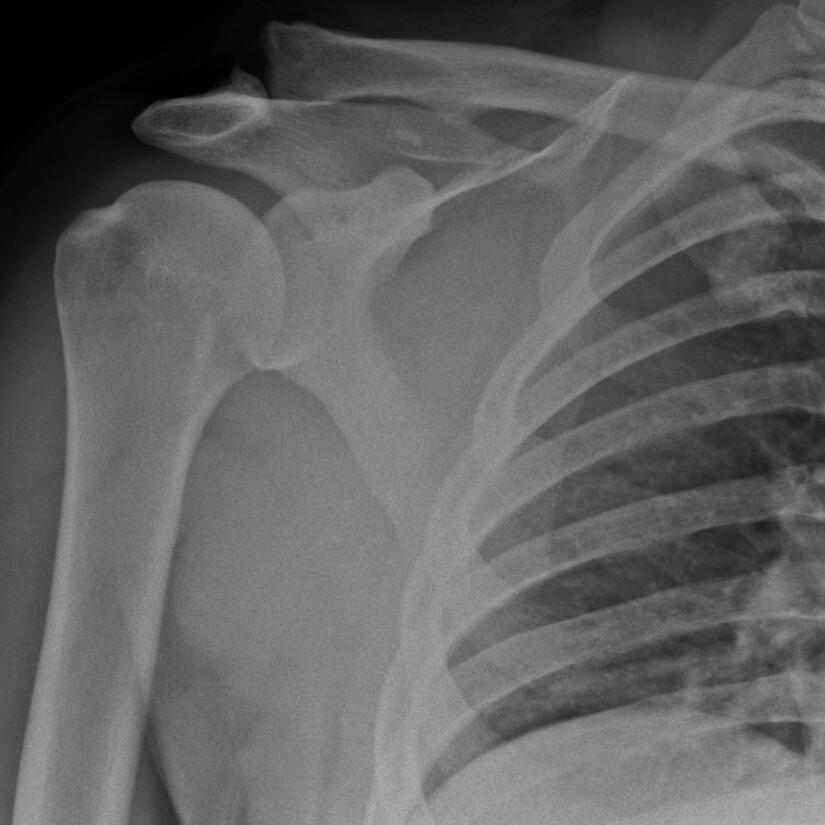

Traumatic AC joint dislocation (X-ray)